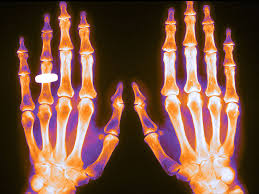

¿La educación patrocinada por la industria fomenta el sobrediagnóstico y el tratamiento excesivo de la depresión, la osteoporosis y el síndrome de vejiga hiperactiva?

BMJ Open, 13 de febrero de 2018 Este resumen de 4 años de los eventos patrocinados por la industria sobre tres trastornos sobrediagnosticadas y sobretratadas se encontró que a menudo el objetivo eran los médicos de atención primaria, a menudo se brindaba la cena y que unas pocas empresas patrocinaban la mayoría de los eventos. En la mayoría de los casos, los productos de los patrocinadores no son opciones rentables para el trastorno especificado.